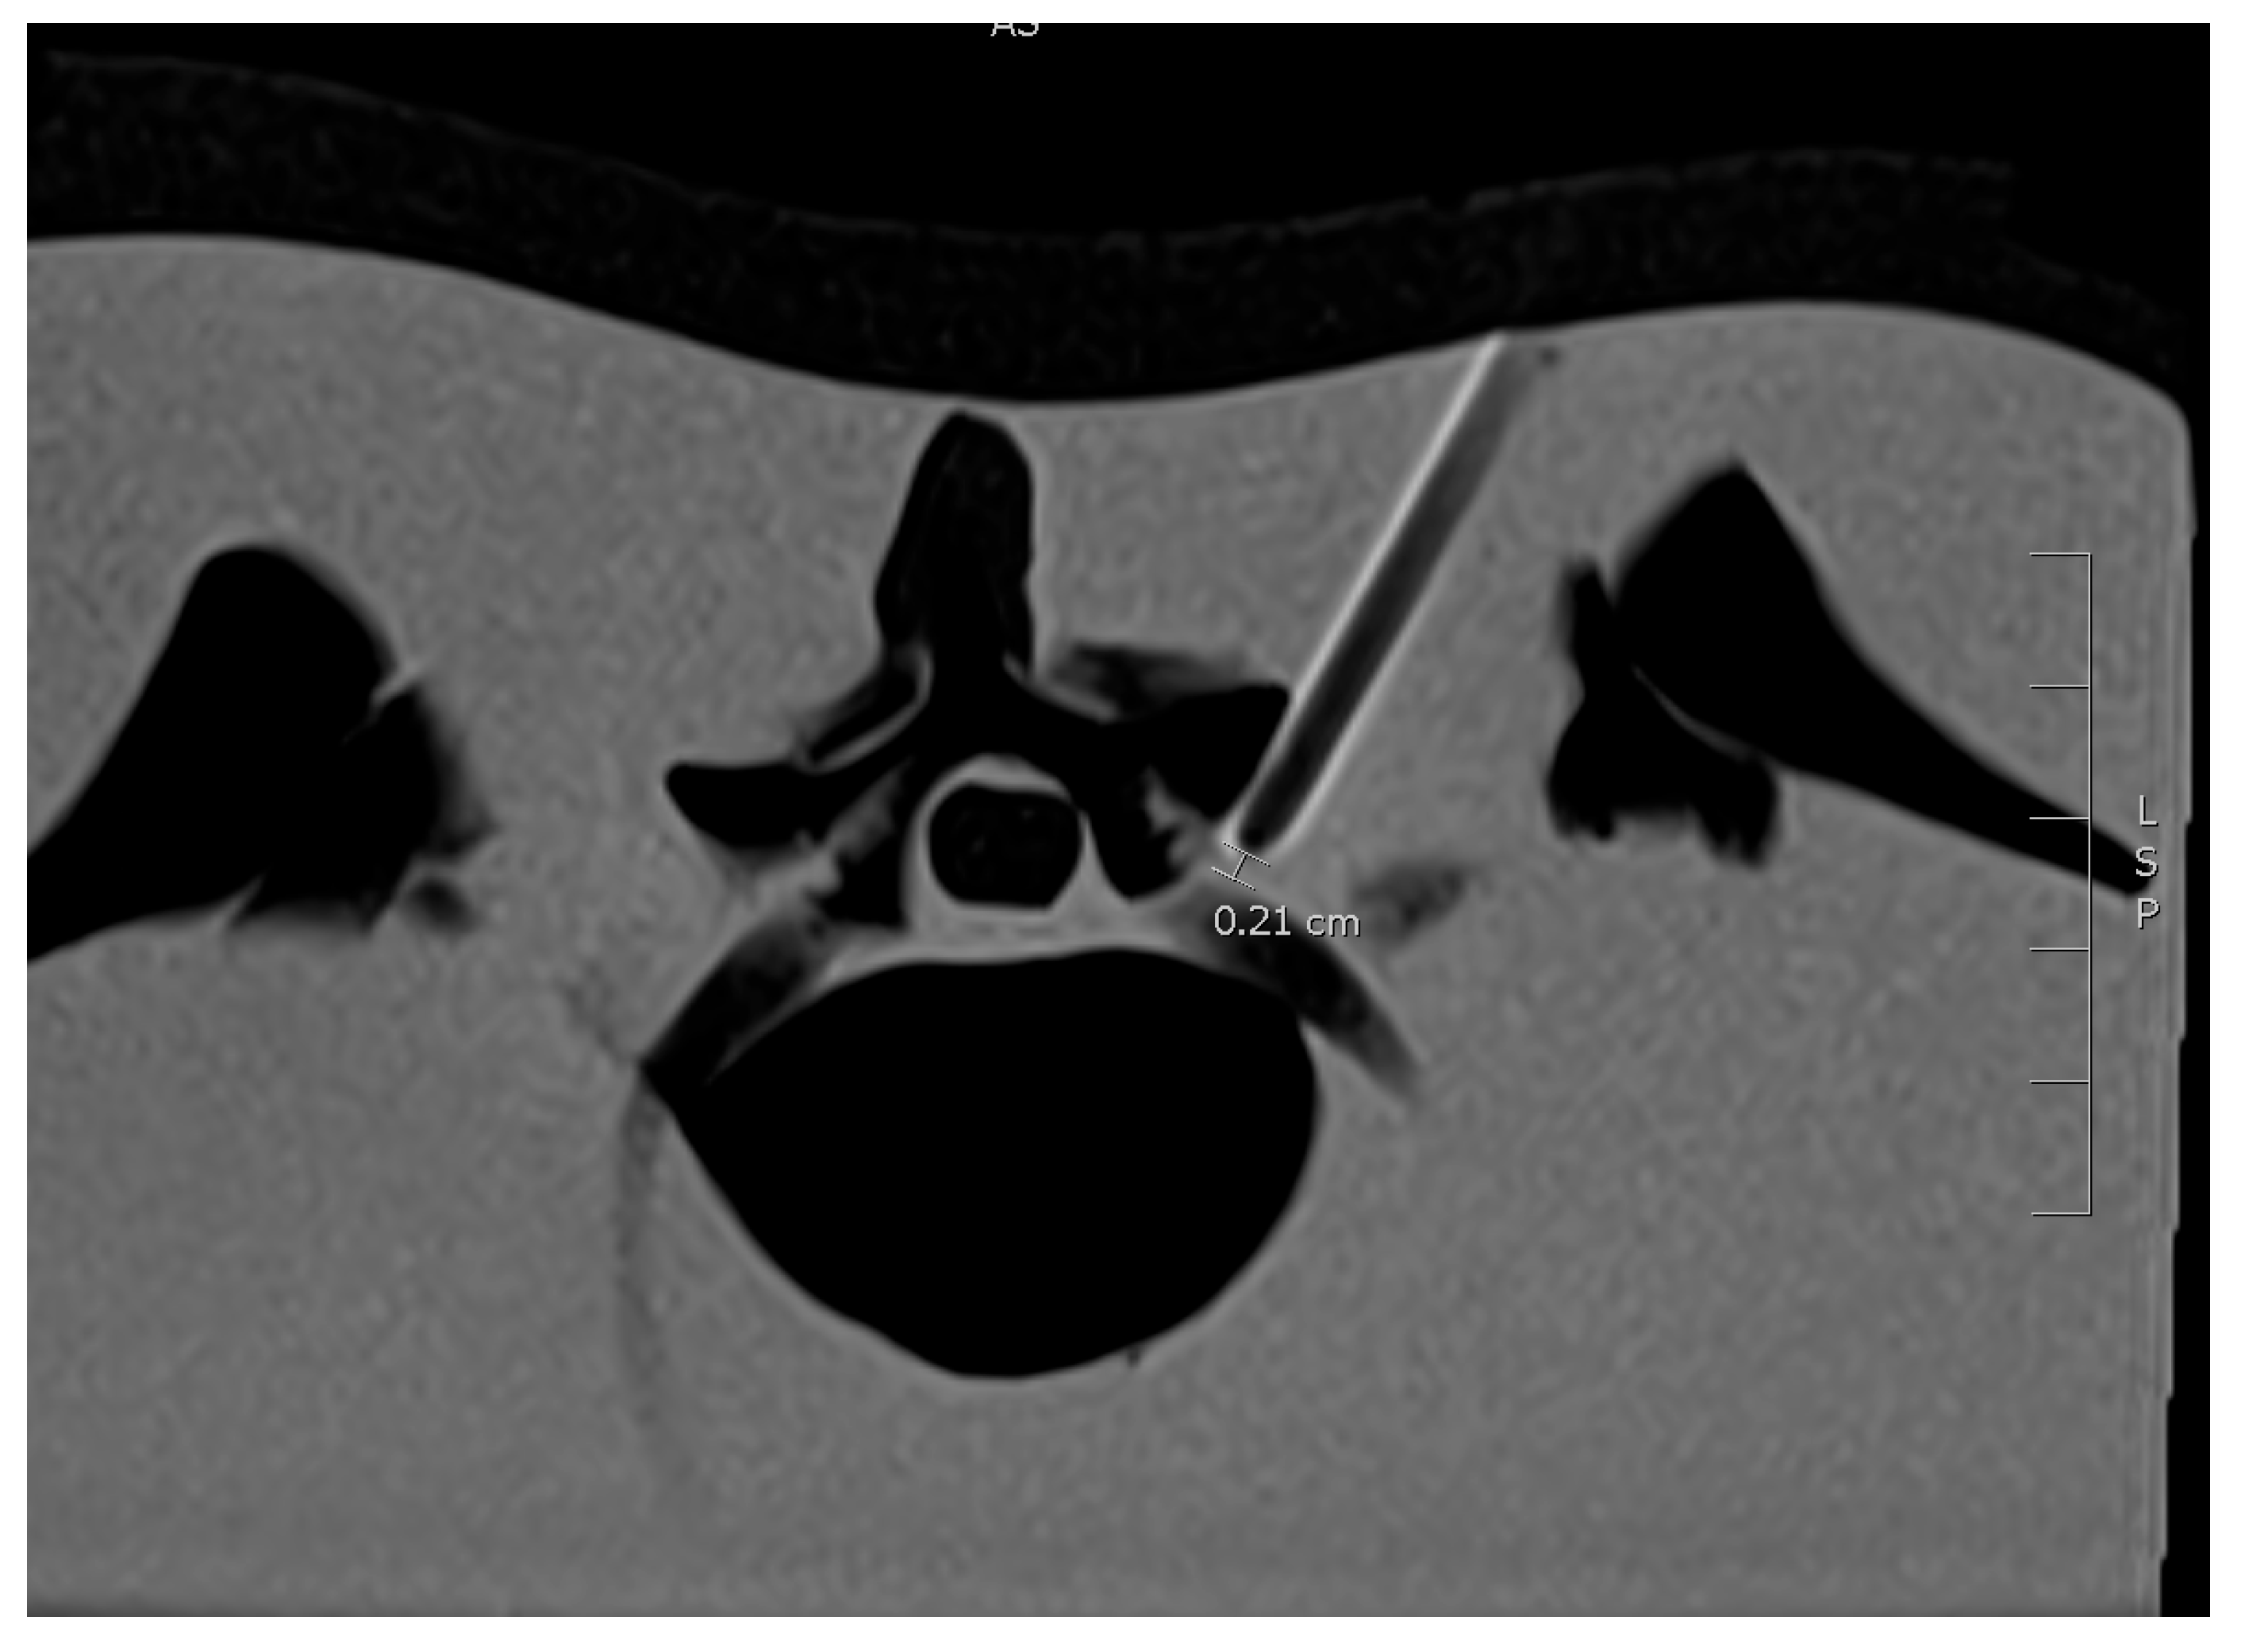

2.1. Study Design

2.4. 3D Laser MDCT Guidance System

4.3. Distance from Needle Tip to the Nerve Root